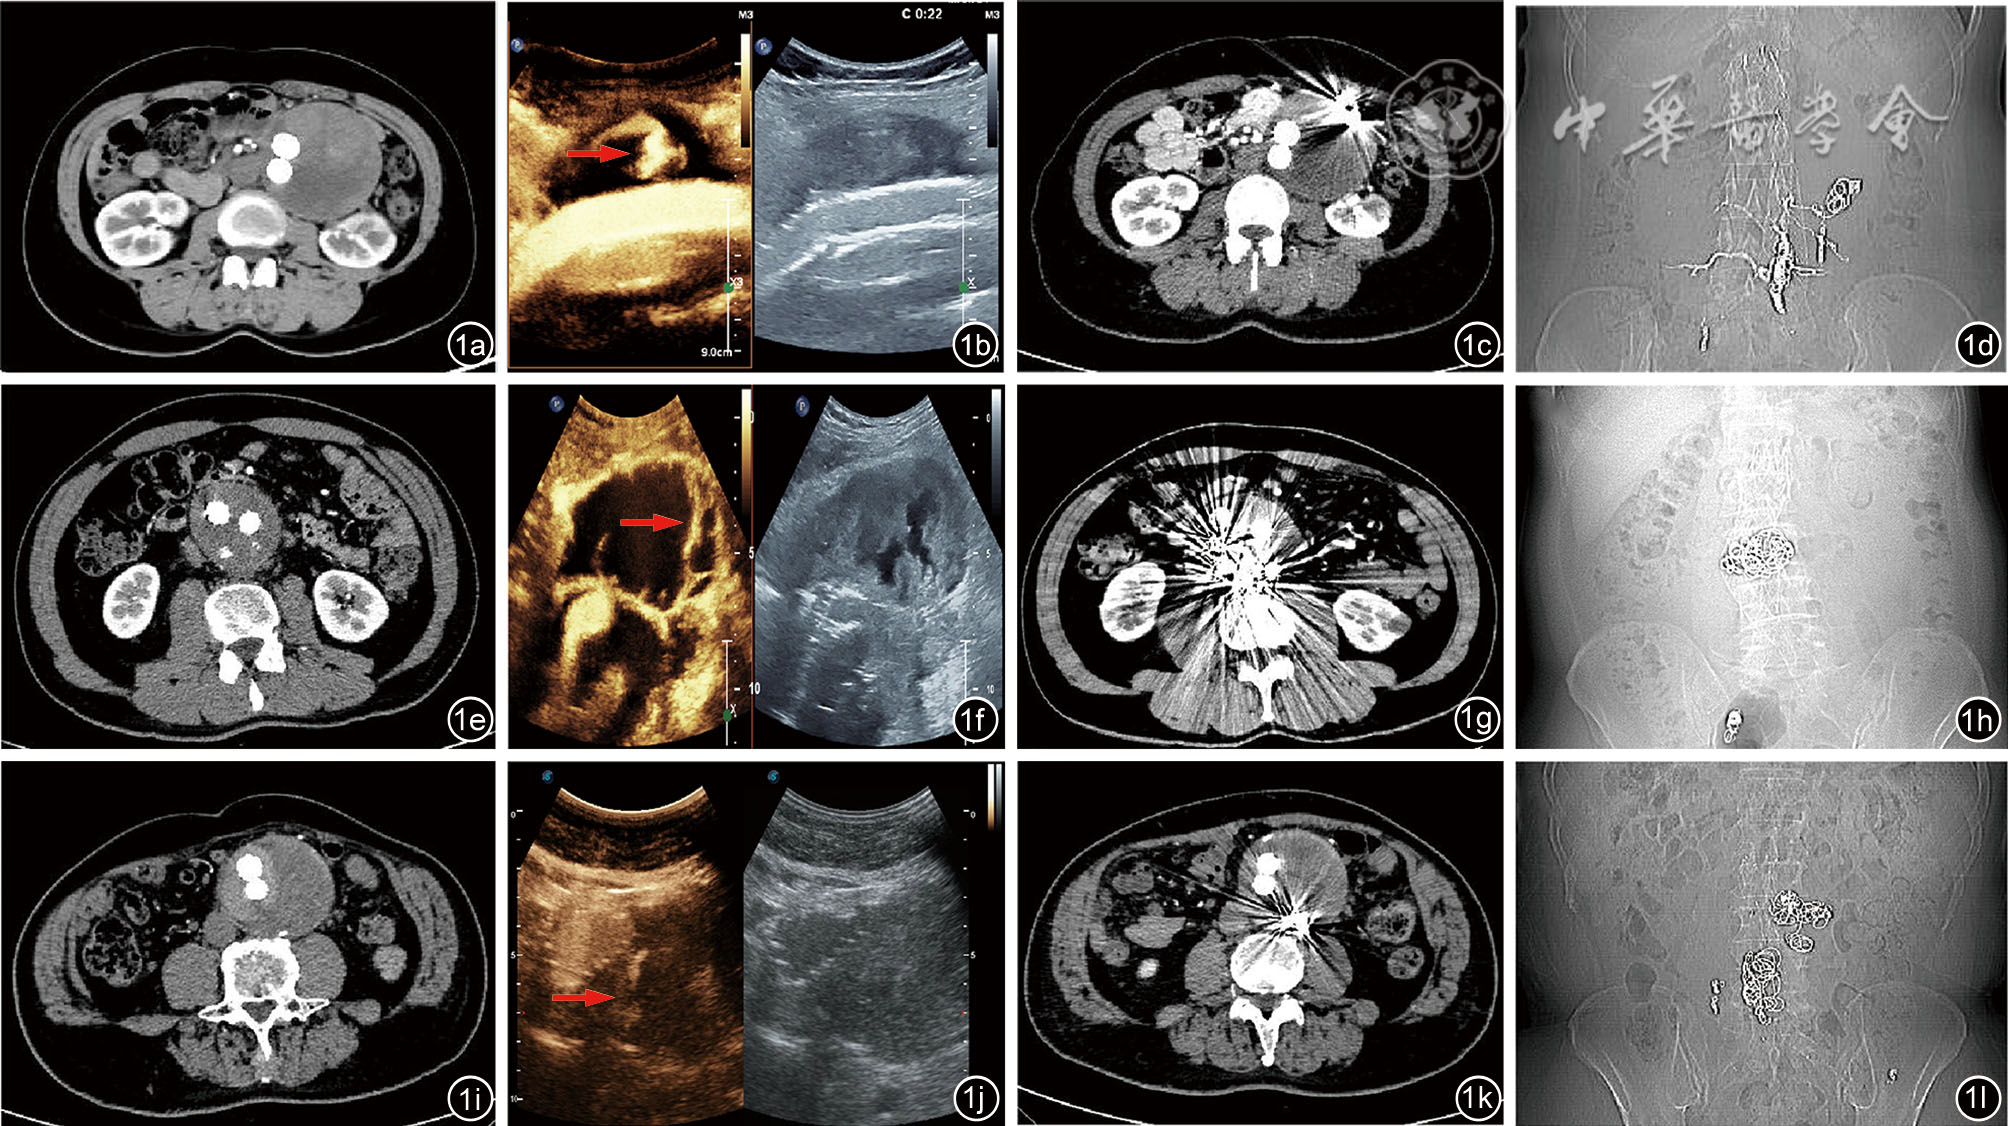

图1 3例患者内漏影像图。图a~d为病例1图像,图e~h为病例2图像,图i~l为病例3图像。图a、e、i分别为术前增强计算机断层血管造影(CTA)图像;图b、f、j为术中超声造影图像,红色箭头示超声造影显示的内漏血管。图c和d为病例1术后8个月CTA图像,图c为增强扫描影像,图d为CTA扫描定位像;图g和h为病例2术后8个月随访CTA影像及定位像;图k和l为病例3术后4个月随访CTA影像及定位像